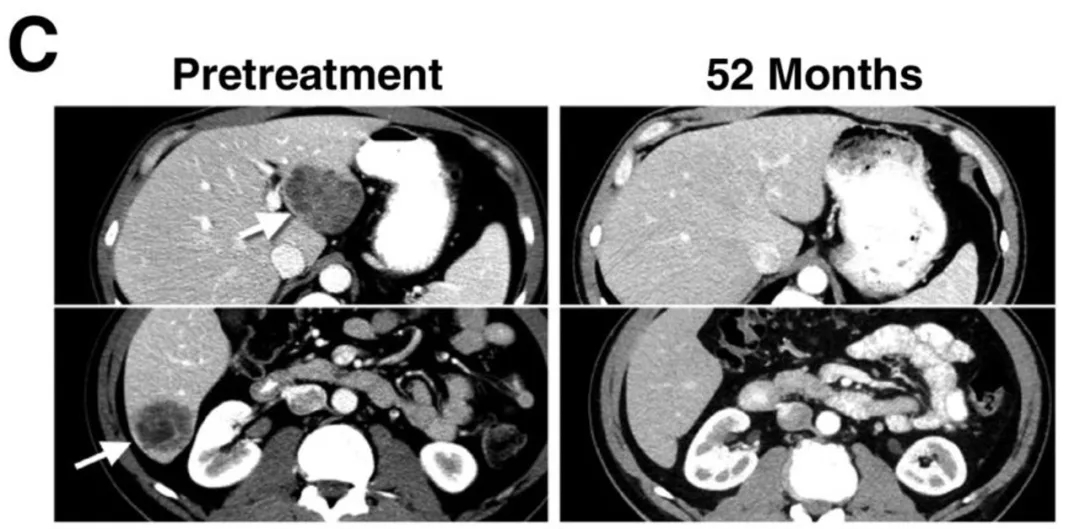

值得关注的是,CT及放射学检查清晰记录了典型患者的肿瘤消退情况:29号患者的肝脏和肺部多发转移灶完全消退(详见下图C/D),疗效维持54个月以上。